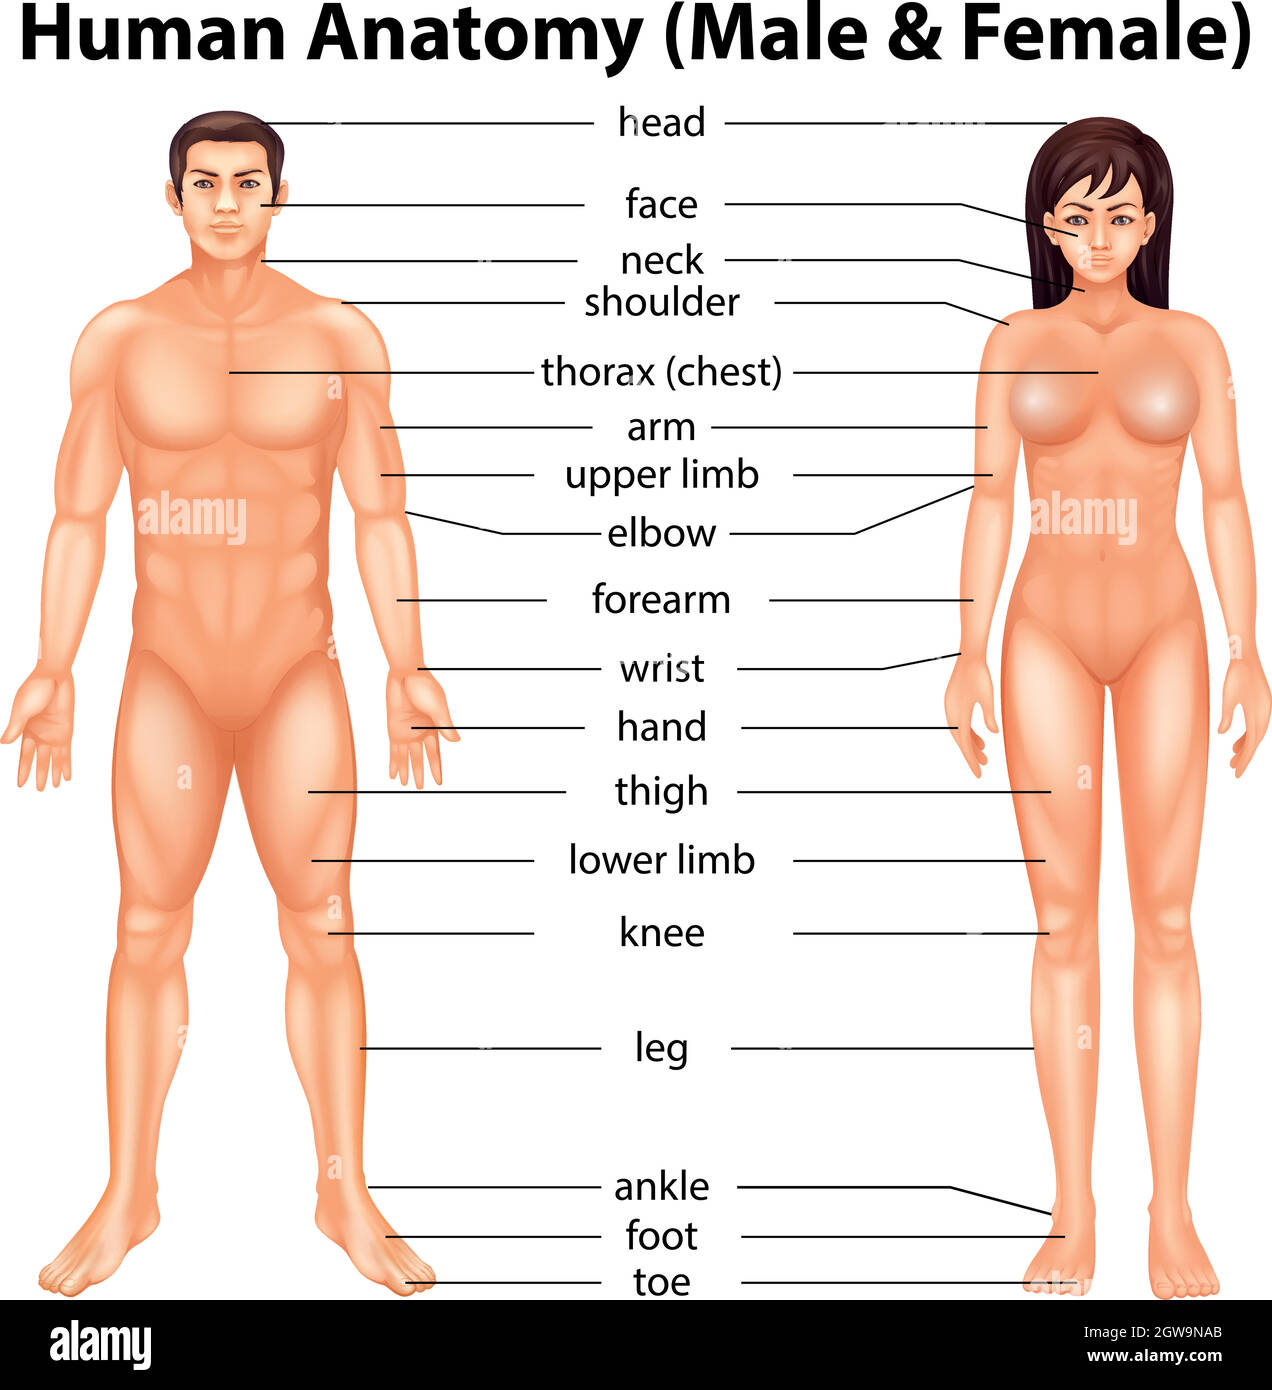

Corteccia cerebrale Immagini Stock Ritagliate

(280)Corteccia cerebrale Immagini Stock Ritagliate